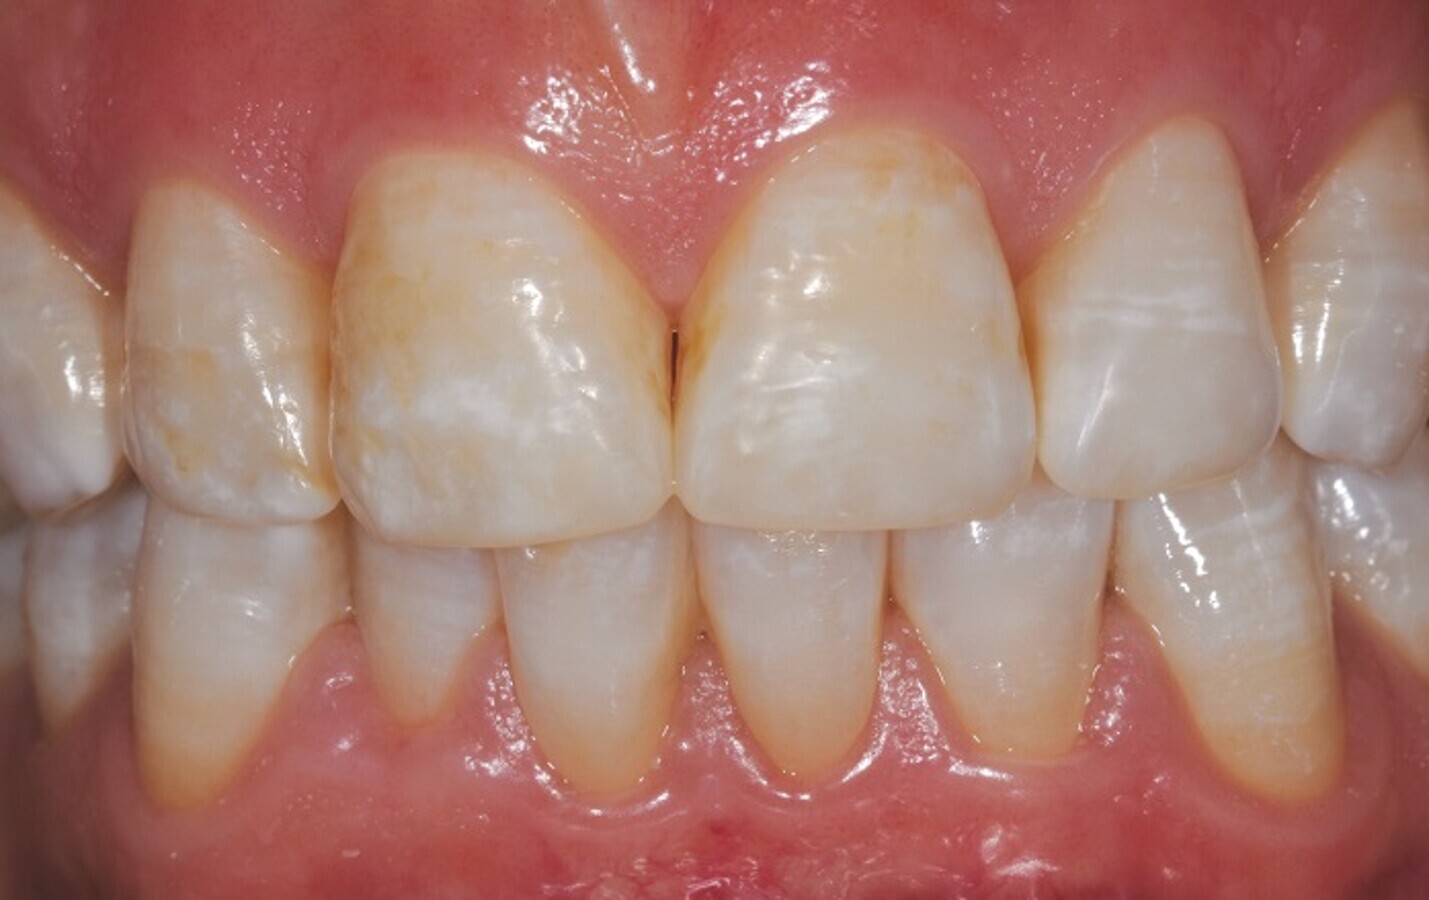

Slika 1: Pred zdravljenjem.

Kljub temu so bili najboljši rezultati doseženi in vivo. V obravnavanem kliničnem primeru je bil namen 37-letne ženske pri obisku zobozdravnika, da bi izboljšala videz svojega nasmeha. Po temeljiti anamnezi in pravilni diagnozi zobne fluoroze (slika 1) je prejela remineralizirajoče zdravljenje na osnovi F-ACP (Biosmalto Mousse Caries, Abrasion & Erosion), ki ga je nanašala v posamezne termoformirane nastavke in uporabljala dvakrat na dan po 20 minut. Svetoval sem ji tudi, naj si v naslednji uri po uporabi pene ne izpira ust, ne pije, ne zaužije hrane in ne kadi. Pacientko smo prosili, naj nastavke dosledno uporablja, vsakih 30 dni hodi na preglede in zdravljenje dopolni z remineralizirajočo zobno pasto Biosmalto Caries, Abrasion & Erosion ter zobno ščetko z mehkimi ščetinami Curasept Soft 012 z Bassovo tehniko ščetkanja.